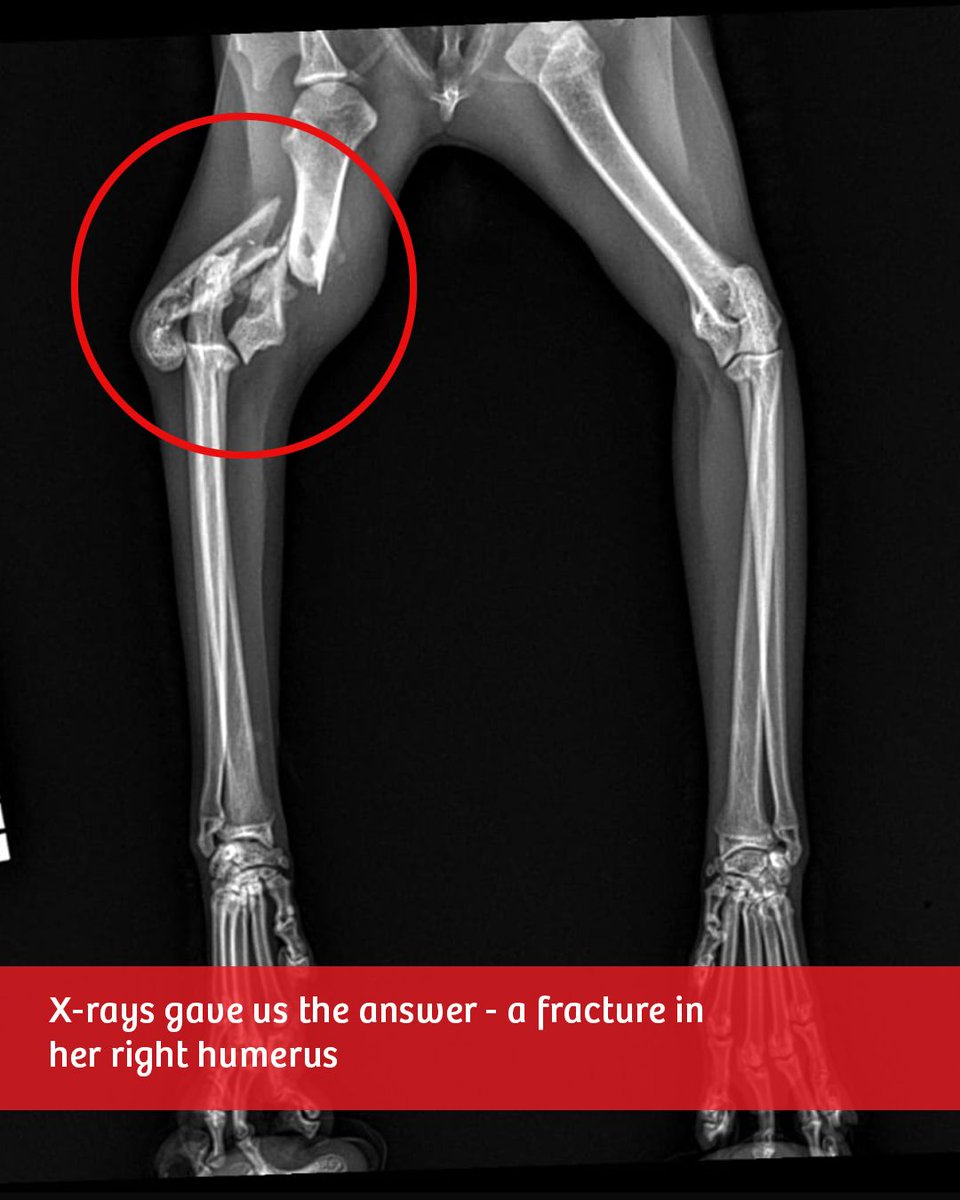

𝐂π₯𝐚𝐫𝐚 𝐍𝐞𝐞𝐝𝐬 π˜πŽπ”π‘ π‡πžπ₯𝐩 🀍 Clara was found limping on the street, quietly struggling on her own. X-rays showed a fracture in her right humerus, and unfortunately, amputation is the only option for her to live without pain.